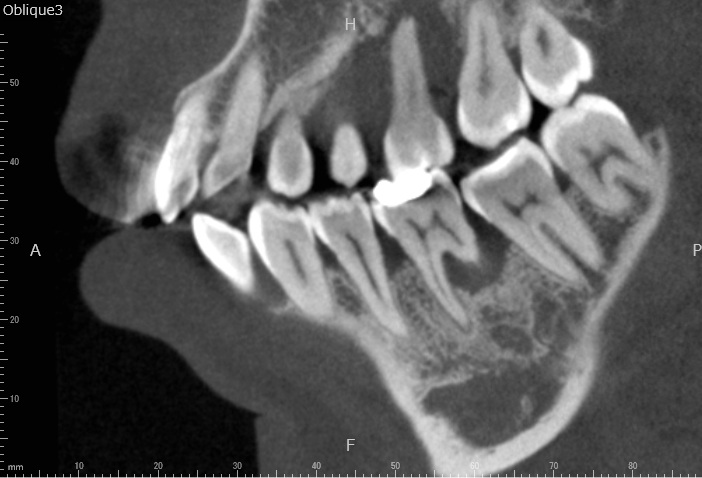

Case2

術前

術中

術後

| 治療名 | 再生療法 |

|---|---|

| 治療説明 | 右下6に重度の歯周病があり、通常の歯周治療でも改善しませんでした。歯周組織再生療法を行い、吸収してしまった骨を再生し、今後の歯周病の進行リスクを減らす事ができました。歯肉退縮もあったため同時に結合組織を移植し、骨と歯肉の再生を同時に行っています。 |

| 治療回数・期間 | 6ヶ月 |

| 副作用とリスク | 手術後に出血、腫脹、疼痛が生じることがあります。手術後は術部の創傷安定のためにブラッシング制限、食事制限があります。手術が複数回となることがあります。 |

| 料金(税込) | 再生療法:165,000円 結合組織移植:55,000円 総額:220,000円 |